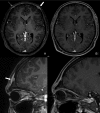

This is a case of a 22-year-old, HIV-negative, male patient with asymptomatic syphilitic osteomyelitis of the skull in the context of secondary syphilis. The diagnosis was made based on serology as well as CT and MRI scans. CT volumetric data was post-processed with cinematic rendering, which is a novel algorithm that allows for a photorealistic visualization of the lesions. Imaging and follow-up scans after treatment confirmed the diagnosis without the need to perform invasive procedures such as a biopsy.